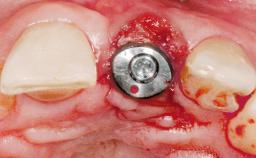

Immediate Flapless Placement of an Implant in a Maxillary Left Central Incisor Site

A 42-year-old female patient was referred to our clinic at the School of Dentistry of the University of São Paulo in November 2004, presenting a deficient restoration in the upper left central incisor. The clinical examination revealed no gingival retraction or any signs of gingival inflammation and, therefore, previous periodontal treatment was not considered. The patient presented a high lip line at full smile and a thin tissue biotype. This combination characterized a high-risk situation from an anatomic point of view, which required careful preoperative planning and cautious surgical execution.

Type of Implants One-Piece

Placement Protocol Immediate implant placement

Loading Protocol Immediate